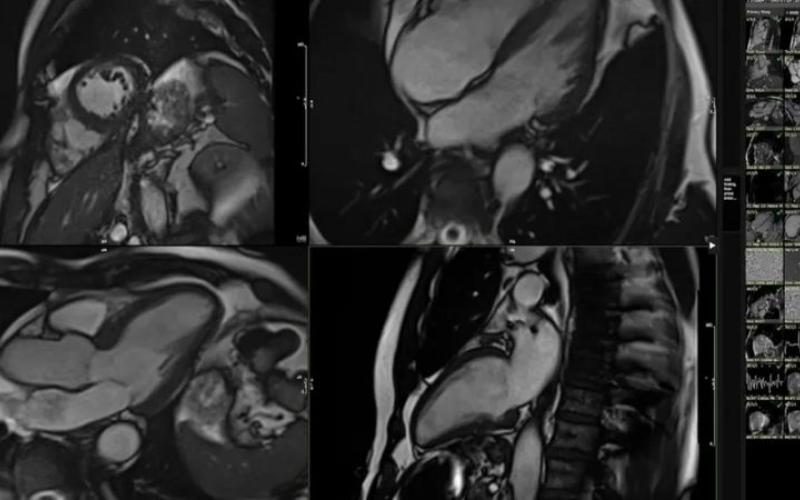

وی، اظهار کرد: تصویربرداری پرتو مغناطیسی یا همان اسکن ام‌آرآی قلب بعد از کمی تحرک بدنی هم بخشی از روند ارزیابی بود. نشانه‌های اولیه پیر شدن زودرس قلب گاهی آن قدر ظریف و نامحسوس است که حتی ممکن است از دید متخصصان قلب هم پنهان بماند. اما هوش مصنوعی قادر است این کار را انجام دهد چون تصاویر اسکن‌های ۴۰ هزار نفر در شرایط مختلف از نظر سلامت قلبی را همراه با وضعیت سلامت خودشان برای رجوع و مقایسه در اختیار دارد. سیستم صدها مورد جزیی و کوچک را در تکان‌های سه‌بعدی اسکن ام‌آرآی من بررسی می‌کند و با تصاویر پنج‌هزار نفر دیگر در سنین مختلف مقایسه می‌کند که زندگی سالمی داشته‌اند.